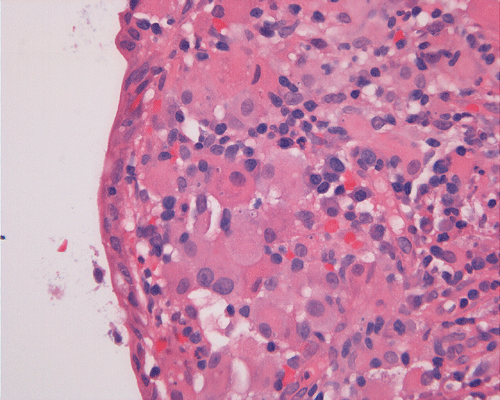

On low-magnification, the biopsy appears to be a piece of colonic mucosa without evidence of necrosis, erosion, or ulcer (Panel A). On medium-magnification, the lamina contains some vaguely formed collections of large cells (Ú in Panel B). On high-magnification, there are many large, round cells with eccentric nuclei. These are macrophages in clusters that are consistent with granulomas.  Many small, grayish to basophilic, vesicle-like structures are present in the cytoplasm (Panel in C). In other areas, these large, round cells do not really form small clusters and are admixed with lymphocytes (Panel D). Again, many small, grayish vesicle-like structures are present in these cells. A grayish to basophilic core is present and is surrounded by halo (Ú in Panel E).  These structures are most suggestive of microorganisms particularly fungus. On periodic acid Schiff (PAS), these vesicles appear bright purple-red (Panel F and G). The basophilic core is also strongly positive for PAS stain (Panel G). These microorganisms appear dark with Gomori methamine silver stain (Panel H and I).

Comment: The pathologic changes in this case are morphologically consistent with histoplasmosis. The patient is immunocomrpomised (HIV-2 positive). Typical to these cases are poorly formed granuloma as illustrated in this case.

In immunocomprised patients that have defective cellular immunity, granuloma formation may be rather indistinct as illustrated in our case. The yeast form of Histoplasma capsulatum is found in tissue and they are usually under 5 mm in diameter and appear as ovoid yeasts.  The lung is the most affected organ. Granuloma formation, typically multiple, with extensive caseous necrosis and a variable amount of calcifications are the typical pathologic changes in the lung. These granulomas are often demarcted from the surrounding tissue by a fibrous wall. Granulomas in the lung can get quite calcified with time. The pulmonary nodules can also enlarge slowly to give a wrongful clinical impression of neoplasm, the so-called histoplasmoma. The living yeast in tissue, often occur in clusters, has a basophilic center and a translucent halo that represents the capsule. They are often engulfed by histiocytes as illustrated in this case. Dead organisms appear eosinophilic and cannot be detected easily in granuloma by hematoxylinj-eosin stain. The microorganism is numerous and can be identified on routine hematoxylin-eosin stain with astute observation and high index of suspicion. Typically, there are numerous yeasts and they are present even in heavily calcified nodules or granulomas.